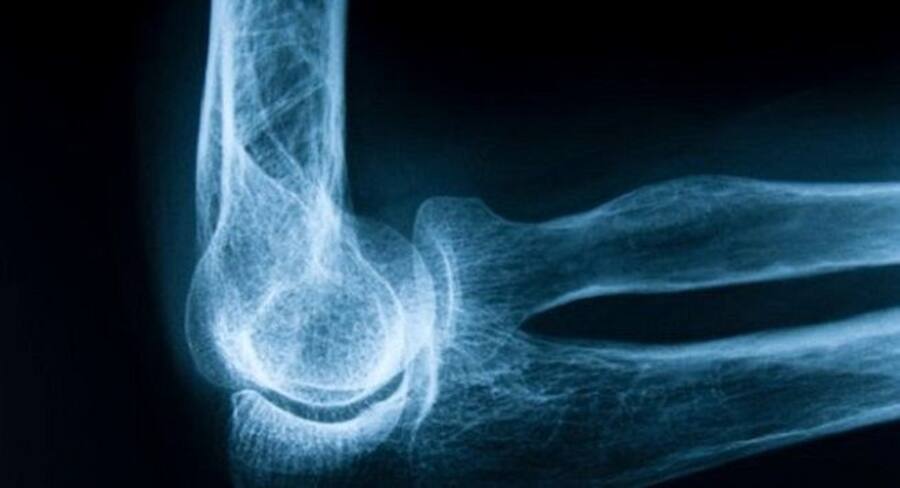

World Osteoporosis Day 2022: Osteoporosis is a silent bone disease characterized by brittle, porous, and weakening bones due to decreased bone mineral density, resulting in frequent fractures of the bone. Lalchawimawi Sanate (PT, LCCE ), Senior Physiotherapist, Cloudnine Group of Hospitals, Sahakarnagar Bangalore shares that according to the International Osteoporosis Foundation, 1 in 3 women over 50 years and 1 in 5 men will be experiencing an osteoporotic fracture in their lifetime.